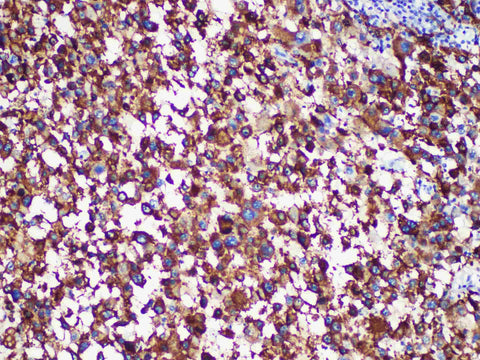

HMB-45 Monoclonal Antibody Stored at -20°C

Applications IHC-P

Tissue Specificity melanoma

HMB45 is a melanoma-associated antigen that is mainly expressed in immature melanocytes. It was also expressed in activated and neoplastic melanocytes and other neural crest-derived tumors. It was also expressed in normal breast epithelium, some normal sweat glands, sweat gland-derived tumors and angiomyolipoma, and occasionally in carcinoma. "It is more specific than S-100 or NKl/C3 for the diagnosis of malignant melanoma, but the sensitivity is less than 90%, especially in metastatic melanoma."